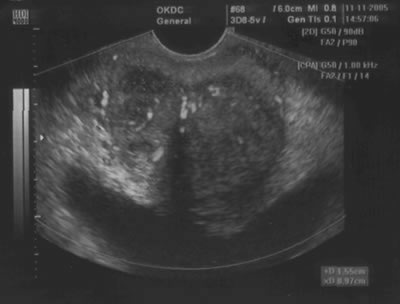

Объем предстательной железы: медицинские аспекты